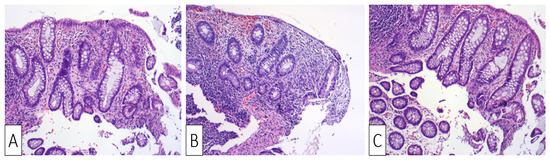

| Our patient | Male, 30 | Colicky left lower quadrant abdominal pain and bloody diarrhea | Negative fecal culture, positive toxins A, B, and GDH | Idiopathic | Several superficial longitudinal ulcerations with luminal narrowing spanning from sigmoid to the descending colon | Desquamation of superficial epithelium with focal necrosis, loss of superficial glands, edematous and necrotic lamina propria | Oral Vancomycin, symptoms resolved within two days of hospitalization |

| Okada et al., 1997 [30] | Male, 52 | Crampy lower abdominal pain followed by bloody diarrhea | Positive fecal culture and strongly positive D-1 toxin | Three-day use of Cefteram for gingivitis | Edematous mucosa with multiple longitudinal shallow ulcers, erosions, and luminal narrowing | Desquamation of superficial epithelium with crypt degeneration, fibrinous exudates in lamina propria, and mild neutrophilic infiltration | Supportive treatment, symptoms resolved by third day of hospitalization |

| Veroux et al., 2007 [31] | Female, 42 | High fever, diffuse abdominal pain with tenderness and bloody diarrhea | Positive toxins | Two weeks after renal transplant; CDI colitis was complicated by CMV colitis | Edematous mucosa with patchy erythema and longitudinal ulceration | Mucosal inflammation, hemorrhage, with leukocytoclastic vasculitis and lymphoplasmacytic perivascular infiltrate | Metronidazole and oral Vancomycin for seven days with no improvement; patient underwent subtotal colectomy but passed away two weeks later |